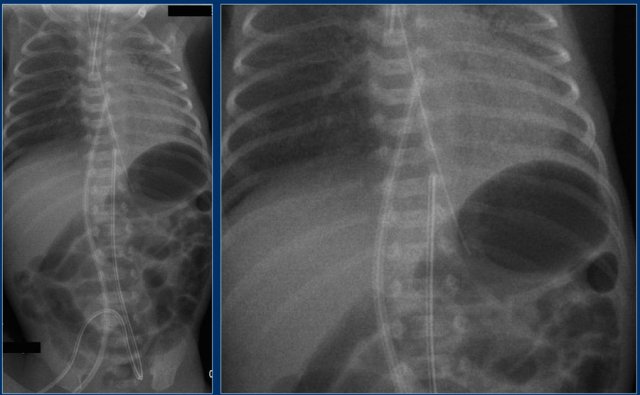

Umbilical artery line (3)

First study the images.

Then continue reading.

The findings are:

1. Malposition of umbilical artery line, folded in the abdominal aorta.

Umbilical artery line (4)

1. Deep position of umbilical artery line, in aortic arch.

2. Umbilical vein line with tip in right portal vein.